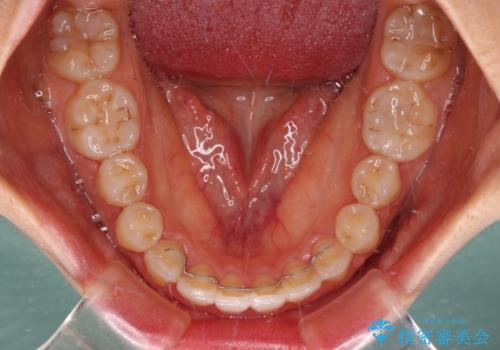

カリエールディスタライザーを併用したことで、確実かつ短期間で治療を終えることができました。